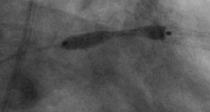

Druckdrahtmessung bei fraglich  relevanter Stenose (FFR / iFR Messung,hier wird  gemessen,  ob die erkennbare Engstelle die  Durchblutung behindert)